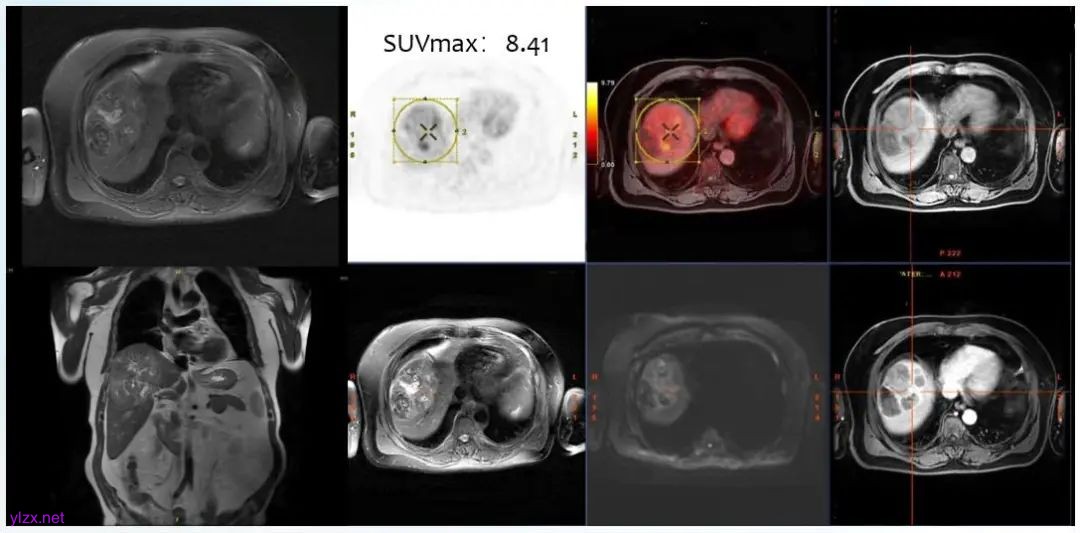

影像学评估:

图1. PET-MRI 功能影像特征

① 根据BCLC 分期B进一步细分为B2(well-defined,超米兰标准);

② PET-MRI呈现高摄取征象;